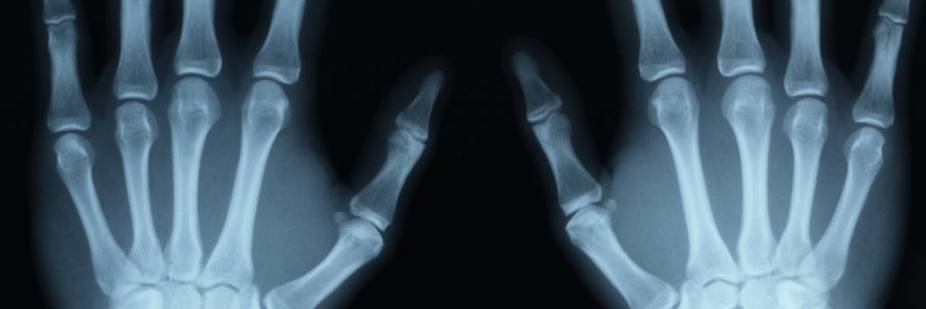

| Description | : | X-radiation (composed of X-rays) is a form of electromagnetic radiation. X-rays have a wavelength in the range of 0.01 to 10 nanometers, corresponding to frequencies in the range 30 petahertz to 30 exahertz (3×10 Hz to 3×10 Hz) and energies in the range 100 eV to 100 keV. They are shorter in wavelength than UV rays and longer than gamma rays. In many languages, X-radiation is called Röntgen radiation, after Wilhelm Röntgen, who is usually credited as its discoverer, and who had named it X-radiation to signify an unknown type of radiation. Correct spelling of X-ray(s) in the English language includes the variants x-ray(s) and X ray(s) |

X-ray image of a child who visited ImageCare after swallowing a penny:

This patient came in after a fall down the stairs. The patient had an x-ray of their tibia-fibula and a fracture was discovered.